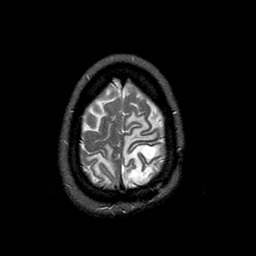

MR Study #1 -- Slice #45